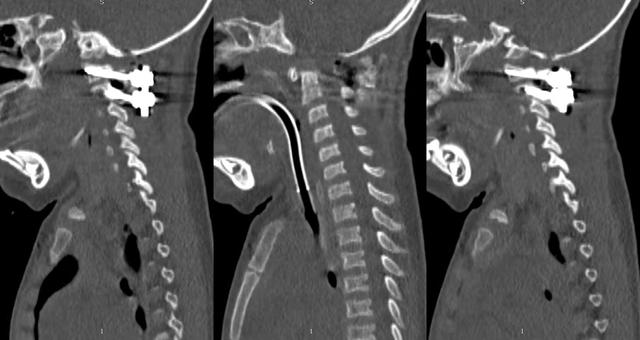

al-align:top;”> 孩子,望你早日康复! 这是一个关于 2岁宝贝的故事 为何这个幼儿平地摔倒,外表毫无受伤痕迹,却出现全身瘫痪,甚至呼吸功能衰竭? …… 为何凌晨时分,重医一院急诊科传来了救护车急促的汽笛声? …… 病史 患儿女,2岁零11个月; 于家中玩耍时平地跌倒致短暂意识丧失,苏醒后四肢瘫痪,自主呼吸微弱,病情危急! 为什么? 影像 患儿在当地医院作了急诊CT检查,发现…… CT显示:寰枢关节不稳 MRI:患儿呼吸不好,病情已不允许作了 分析 1. 尽管没有MRI检查,但根据CT显示的寰枢椎不稳,结合患儿四肢瘫痪,自主呼吸微弱的症状,颈延髓损伤明确; 2. 临床诊断:1)寰枢椎脱位 2)颈延髓损伤 怎么办? 方案 刻不容缓,做急诊手术准备! 寰枢关节不稳必须立即解决,否则有延髓再损伤的风险! 急诊手术:“寰枢椎复位+颈1-2融合内固定术+后路寰枕减压” 难点 患儿年龄小且发育较差,身高较同龄幼儿少10cm,体重仅仅11kg,上颈椎手术本就属脊柱高危手术之一,而幼儿的上颈椎骨质细小,在幼儿的上颈椎进行内固定手术,更是难上加难; 经验 重庆医科大学附属第一医院虽然是一所主要面向成人的综合性医院,但本院神经外科脊柱亚专业组,在幼儿脊柱手术方面具有丰富经验,尤其是对幼儿上颈椎损伤、颅底凹陷、先天性颅颈畸形、寰枢椎脱位等疾病,手术技术娴熟,成功完成过从2岁至13岁不同年龄幼儿的上颈椎手术。 既往病例文章分享: # 从13岁到2岁 # 一例“复杂”幼儿颅颈畸形 # 挑战幼儿 —— 3岁11月颅颈畸形手术病例分享 # 病例分享 || 幼儿复杂颅颈畸形 ……………… 本例患儿的手术在入院后2小时立即进行,并成功完成。解决了患儿寰枢椎不稳的风险,为其后续治疗的安全性提供了强有力的保障。 术后情况 术后CT示寰枢椎完美复位,寰枕区减压充分, 避免了患儿颈延髓神经功能二次损伤可能,为康复争取时间! 小宝贝术后虽然颈椎稳定了, 也减压了。 但是一时还无法脱离呼吸机, 也无法离开监护室, 无法见到自己爸爸妈妈! 不要害怕,宝贝! 重医一院神经外科脊柱亚专业组 和神经重症亚专业组的叔叔阿姨们 以及神经外科的护士小姐姐们, 会一直守护在你身边, 为你保驾护航! 宝贝加油! 相信你一定能战胜病魔,茁壮成长! 老晏说 幼儿脊柱疾病,亦在重庆医科大学附一院神经外科!